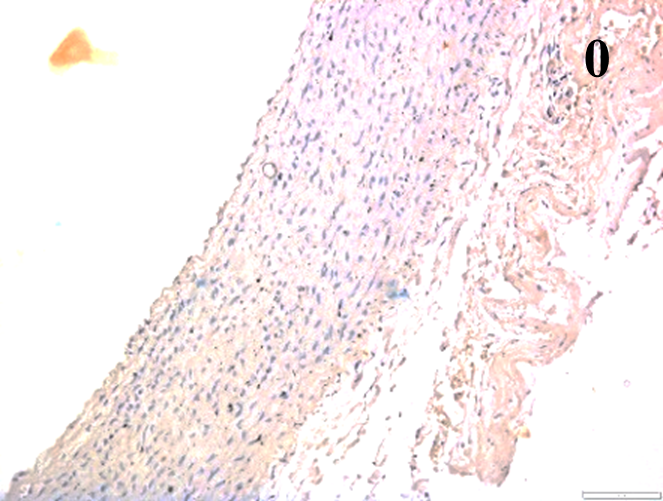

According to the percentage endothelial staining of cells, semi-quantitative

scores were applied. Score: 0 (negative); 1+ (1–10% positive cells); 2+

(11–25% positive cells) and 3+ (